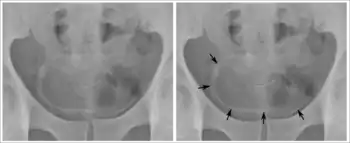

Calcifications on bladder wall caused by urinary schistosomiasis

Cystitis refers to infection or inflammation of the bladder. It commonly occurs as part of a urinary tract infection.[23] In adults, it is more common in women than men, owing to a shorter urethra. It is common in males during childhood, and in older men where an enlarged prostate may cause urinary retention.[23] Other risk factors include other causes of blockage or narrowing, such as prostate cancer or the presence of vesico-ureteric reflux; the presence of outside structures in the urinary tract, such as urinary catheters; and neurologic problems that make passing urine difficult.[23] Infections that involve the bladder can cause pain in the lower abdomen (above the pubic symphysis, so called "suprapubic" pain), particularly before and after passing urine, and a desire to pass urine frequently and with little warning (urinary urgency).[23] Infections are usually due to bacteria, of which the most common is E coli.[23]